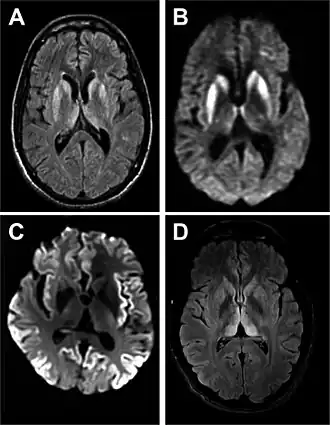

Ressonância magnética de DCJ esporádica[2]

A DCJ é causada por proteínas denominadas priões.[4] Os priões são proteínas mal enoveladas que fazem com que proteínas corretamente enoveladas se tornem elas próprias desenoveladas.[3] Cerca de 85% dos casos ocorrem por razões desconhecidas, enquanto cerca de 7,5% dos casos são herdados de um dos progenitores de forma autossómica dominante.[3][5] A doença pode também ser transmitida por exposição ao cérebro ou tecidos da medula espinal de uma pessoa infetada.[3] Não há evidências de que possa ser transmitida entre pessoas por contacto normal ou transfusão de sangue.[3] O diagnóstico da doença requer que sejam descartadas outras potenciais causas e pode ser complementado por electroencefalograma, punção lombar ou ressonância magnética.[3]